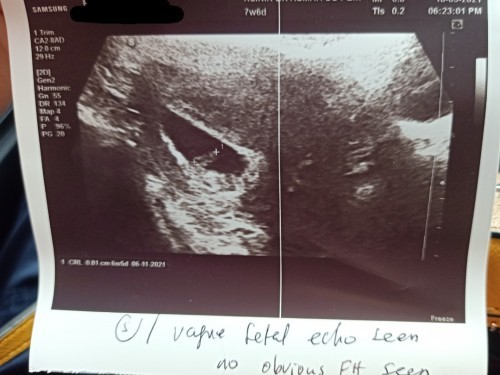

Normal ke 7week 5day tak nampak jantung lagi...dan bila scan janin 6week 5day...#firstbaby

normal..sy dlu lmbt juga dh dkt 10week ke 9week br nmpk

nrml sis..8w ke ats bru npk sume